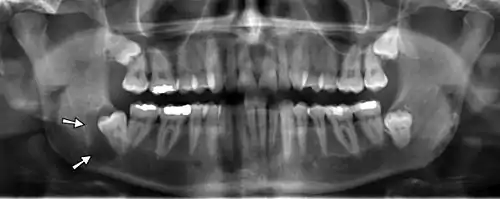

Panoramic radiograph showing horizontally impacted lower wisdom teeth.